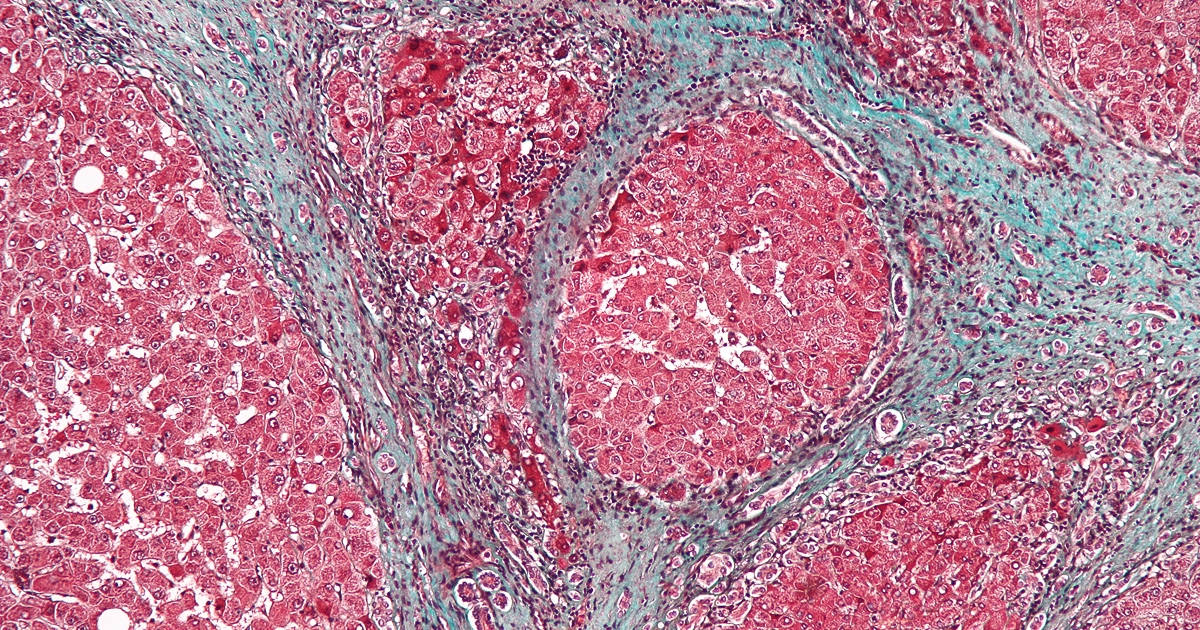

Podľa zistení vedcov mali ľudia vystavení PCE trojnásobne vyššie riziko vzniku závažnej fibrózy pečene: ochorenia, ktoré môže prerásť do rakoviny pečene, zlyhania orgánu alebo smrti. Výskum tiež potvrdil jasný trend: čím vyššia miera expozície, tým väčšie riziko.